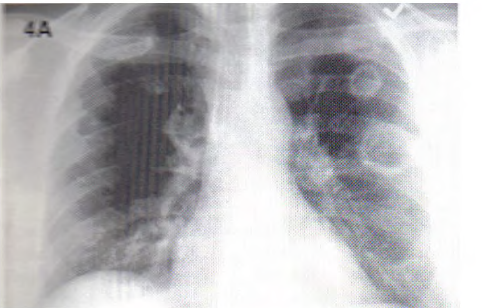

Bizarre Presentation of Huge Primary Pulmonary Leiomyoma